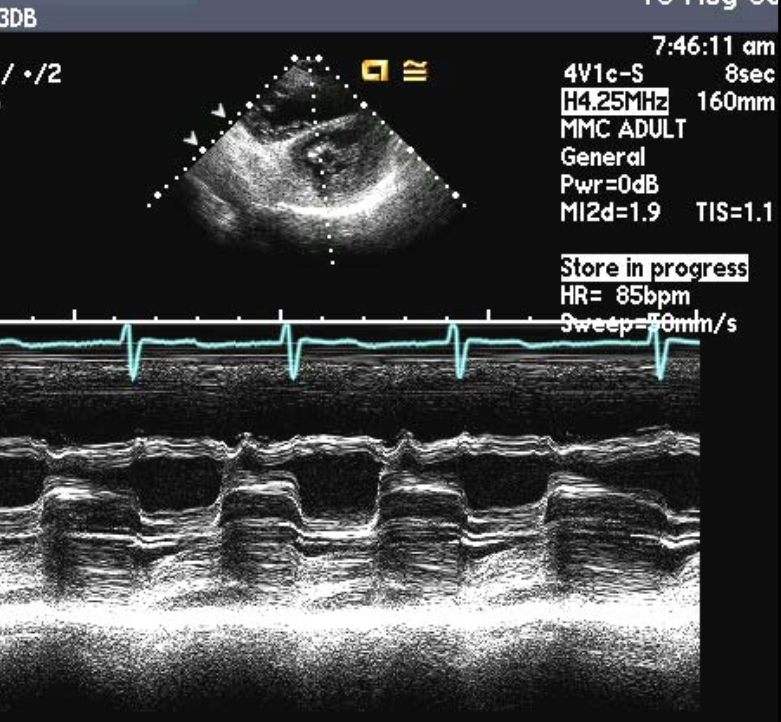

what should you always report with the MV gradient?

HR

Diagnosis?

MS